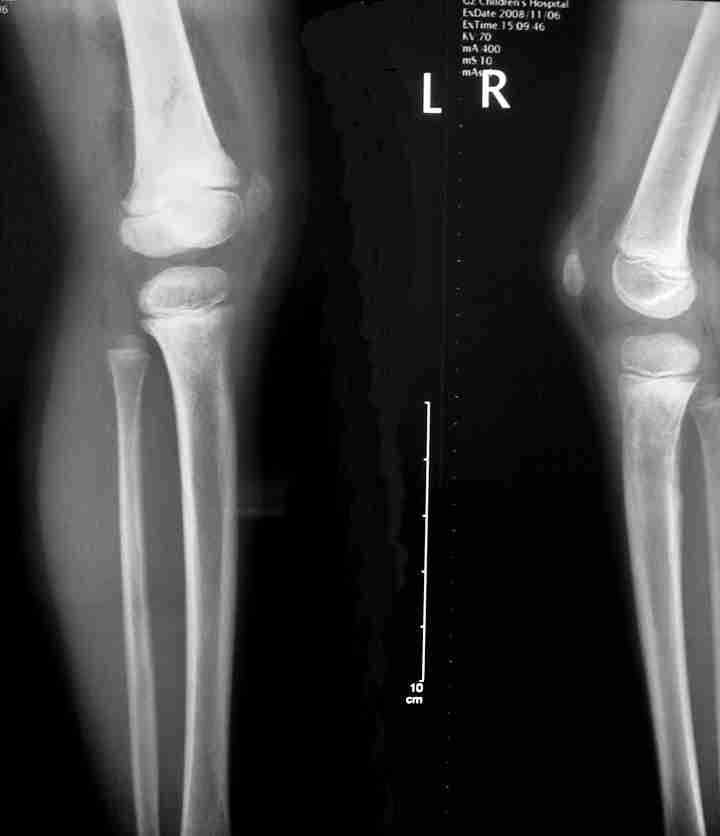

男孩5岁,下肢疼痛1年余。

多骨溶骨性破坏,累及干骺端,可见骨硬化增生,可见软组织肿块,有明显骨膜反应,患者男性,5岁,病史一年,考虑骨恶性肿瘤,成神经细胞瘤,ewing瘤,骨母细胞肉瘤及转移等可能性大,另不除外黄脂瘤